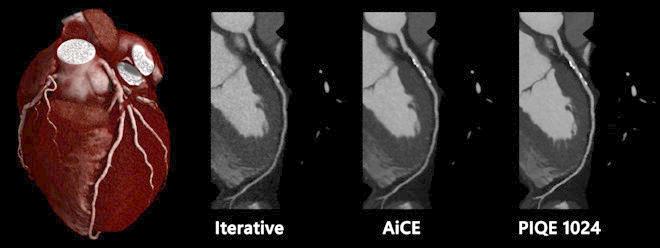

After the successful introduction of Advanced intelligent Clear-IQ Engine (AiCE), Precise IQ Engine (PIQE) is the next step in Deep Learning Reconstruction (DLR) bringing together extraordinary spatial resolution and reduced noise. PIQE shows sharper anatomical details in 1024 image matrix for better delineation of small anatomical

structures for a more accurate diagnosis of complex pathologies, particularly in cardiology, oncology, or paediatric imaging.

PIQE is a Deep Learning Reconstruction algorithm that maximises the inherent resolution of a CT to provide Super Resolution 1024 matrix images. PIQE images show sharper anatomical detail for better delineation of small anatomical structures for a more definitive diagnosis.

“The benefit of PIQE 1024 is that it gives us much higher spatial resolution without increasing radiation dose. As it improves spatial resolution, we can image coronary arteries with calcification and stents and we can reduce blooming artefacts. We’ve only had it five weeks, but we are much more confident in our diagnosis because the resolution is much higher,” Dr. Bull added.

Cardiac CTA with different reconstructions algorithms of the LAD showing increased spatial resolution with PIQE 1024.